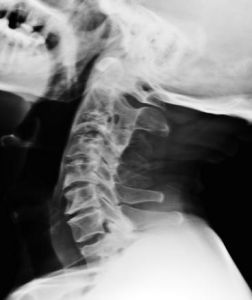

阻滯椎阻滯椎是脊柱的先天性骨性融合,常累及2個或2個以上椎體,受累部位2個椎體往往顯示完全性骨融合,除椎體處,椎弓根亦相互融合。受累椎體之間前後徑變短且前面凹陷,融合椎前緣多平滑呈弧行凹陷,在骨性融合的兩個椎體間相當於椎體間隙部位變細,如“蜂腰狀”。椎管短小,棘突完全或部分融合。多合併椎管和附屬檔案及椎間孔畸形。

影像上有7個特點:1、融合椎前緣光滑,有弧性凹陷。

2、椎體矢狀徑較正常椎體縮短。

3、椎體融合部縮細,呈“蜂腰狀”。

4、椎體的高度相當於正常椎體加椎間隙的高度。

5、椎管矢狀徑增寬(故:脊髓型頸椎病較少發生)。

6、椎間孔狹窄,呈啞鈴狀或雙腎狀(故:神經根型頸椎病多發)。

7、阻滯椎附屬檔案發生廣泛融合。

常可合併其他肢體或脊柱畸形(本例就合併拇指畸形與第七頸椎隱性脊柱裂 )。

融合椎與下位正常椎體間的椎間盤因應力集中,易導致後天性頸椎間盤突出,引發脊髓症狀。